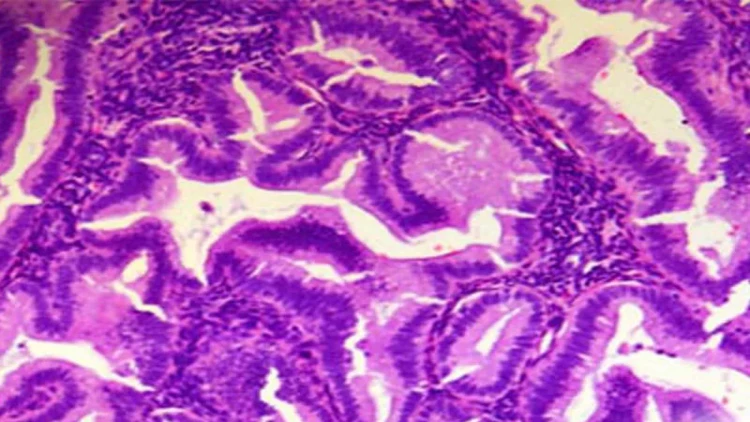

Heyvanların və bitkilərin əksəriyyəti çoxlu sayda kiçik hissəciklərdən ibarətdir. Biz bu hissəcikləri hüceyrə adlandırırıq. Bizim və başqa canlıların orqanizmlərin hüceyrələri daima bölünür. Bu bölünmə prosesi orqanizmə hüceyrələrin inkişaf etməsinə və bərpa olunmasına xidmət edir. Hüceyrənin quruluşunun əsasını protoplazma adlanan maddə təşkil edir. Hər bir hüceyrənin daxilində müəyyən funksiyaları yerinə yetirən kiçik hissəciklər vardır. Onların arasında irsi məlumat daşıyan, xromosom adlanan kiçik elementlər vardır. Hər bir heyvan və bitki növünün hüceyrələrindəki xromosomların sayı fərqlidir. İnsan orqanizmindəki hər bir hüceyrənin tərkibində 46 xromosom vardır. Bizim orqanizmdə hüceyrə bölündükdə əmələ gələn hər yeni hüceyrənin tərkibində eyni sayda, yəni qırx altı xromosom olur. Əgər xromosomların sayı dəyişsəydi, onda insan insan olmazdı. Cinsi hüceyrələr adlanan iki növ hüceyrədən başqa insan orqanizmində bölünmə nəticəsində əmələ gələn bütün hüceyrələr mütləq olaraq 46 xromosom təşkil edır. Bu, kişilərdə spermatozoidlər, qadınlarda isə yumurta hüceyrələridir. Cinsi hüceyrələr də bölünmə prosesi nəticəsində əmələ gəlir, lakin onlar 46 xromosom deyil, bunun yarısısını təşkil edir. Yəni, hər bir kişi və qadın cinsi hüceyrəsi 23 xromosomdan ibarətdir. Mayalanmış yumurta hüceyrəsi adlanan rüşeymin ilk hüceyrəsinin yaranması üçün kişi cinsi hüceyrəsi ilə qadın cinsi hüceyrəsi birləşməlidir. Kişi hüceyrəsinin iyirmi üç xromosomu qadın hüceyrəsinin xromosomları ilə birləşərək yeni hüceyrədəki xromosomların sayını normaya, yəni qırx altıya çatdırır. 46 xromosomdan ibarət olan mayalanmış yumurta hüceyrəsi daima bölünərək iki, sonra dörd, sonra səkkiz hüceyrə əmələ gətirir. Bu proses dölün ana bətnindən çıxdığı vaxta qədər davam edir. Sonra hüceyrələrin bölünməsi insanın tam inkişaf etməsinə qədər davam edir və onun orqanizmin hər bir hüceyrəsi 46 xromosom təşkil edir. İnsan orqanizmində сinsi hüceyrələrin yaranması üçün sonradan birləşsinlər deyə xromosomların sayının ikiqat azalması kor-təbii və təsadüfi proses nəticəsində yarana bilməz. Məgər bütün bunlar hər şeyi yerli-yerində yaradan müdrik Xaliqin varlığını qəbul etmək üçün kifayət deyilmi?